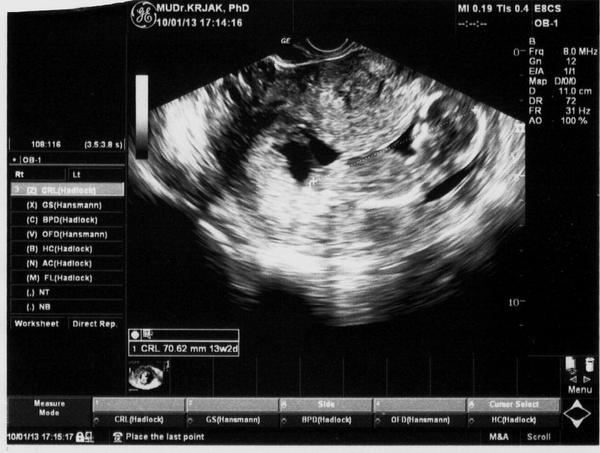

ja mám tiež fotku takú nekvalitnú ,machulku ,ale na sone som si malé poobzerala ,Krajkovič mi všetko vysvetloval kde je rúčka,nožička chrbátik atd...najskôr mi robil sono cez bruško ,ale ked si malé nechcelo dať zmerať noštek tak skúsil sono cez pošvu a to už bolo celkom zle otočené a už mi to bolo aj nepríjemné mám tam predsa menej miesta 😀